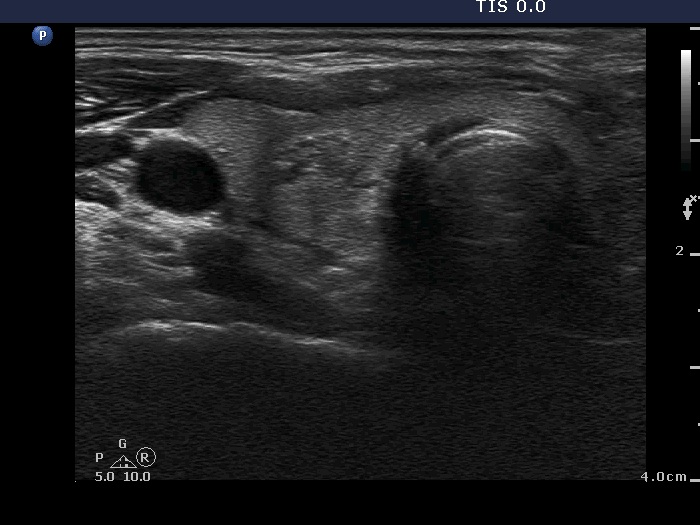

The ultrasound pattern of de Quervain's thyroiditis and that of papillary cancer are very similar: a hypoechogenic lesion with blurred borders are found in both cases. They differ in vascularization statistically but the vascular pattern has only limited practical significance. In the acute phase of de Quervain's thyroiditis the vascularization is generally decreased but even in this case the situation was the opposite. The finding of not one but multiple hypoechogenic areas favored the possibility of subacute thyroiditis.

The relapse of de Quervain's thyroiditis in the contralateral lobe is a very frequent finding but not one year after the appearance of the disease. We supposed that the immunological changes during and after pregnancy explained the relatively late relapse of the disease.